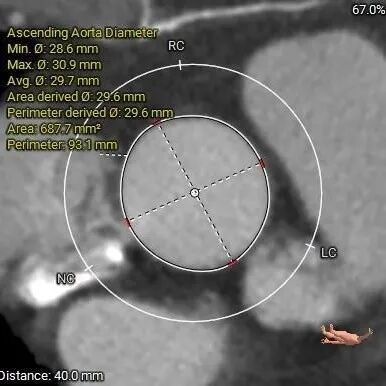

术前CT评估

功能型二叶瓣,瓣叶增厚,R-L间有钙化嵴;大瓦式窦,升主扩张严重横位心

重度钙化,HU 850积分1192mm3

左冠19.4,右冠25.8,综合分析冠脉阻挡风险适中

瓣上多平面分析

•瓦氏窦增宽,STJ及升主扩张,